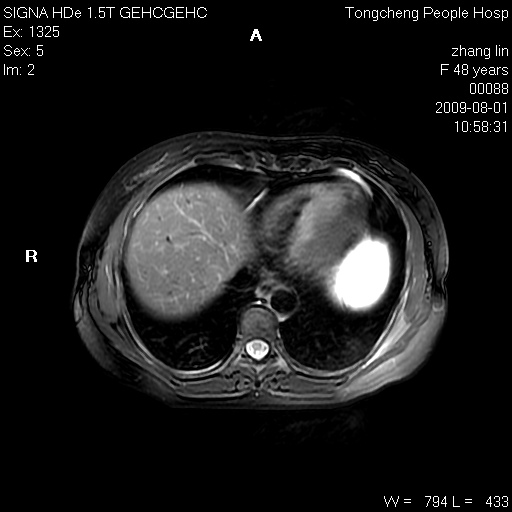

女,48岁。健康体检,彩超发现右肾占位性病变。平素健康。

临床诊断:右肾占位性病变,性质待定(囊肿?肿瘤?)。

上中腹部mr平扫+增强扫描,图像如下:

右肾上极见一类圆形病灶,t1wi呈等信号t2wi呈等高混杂信号,三期增强无强化,边界清---考虑囊肿出血。

同反相位均表现为等信号,病变无强化,考虑含蛋白的囊肿可能,弥散加权相或许有些帮助,